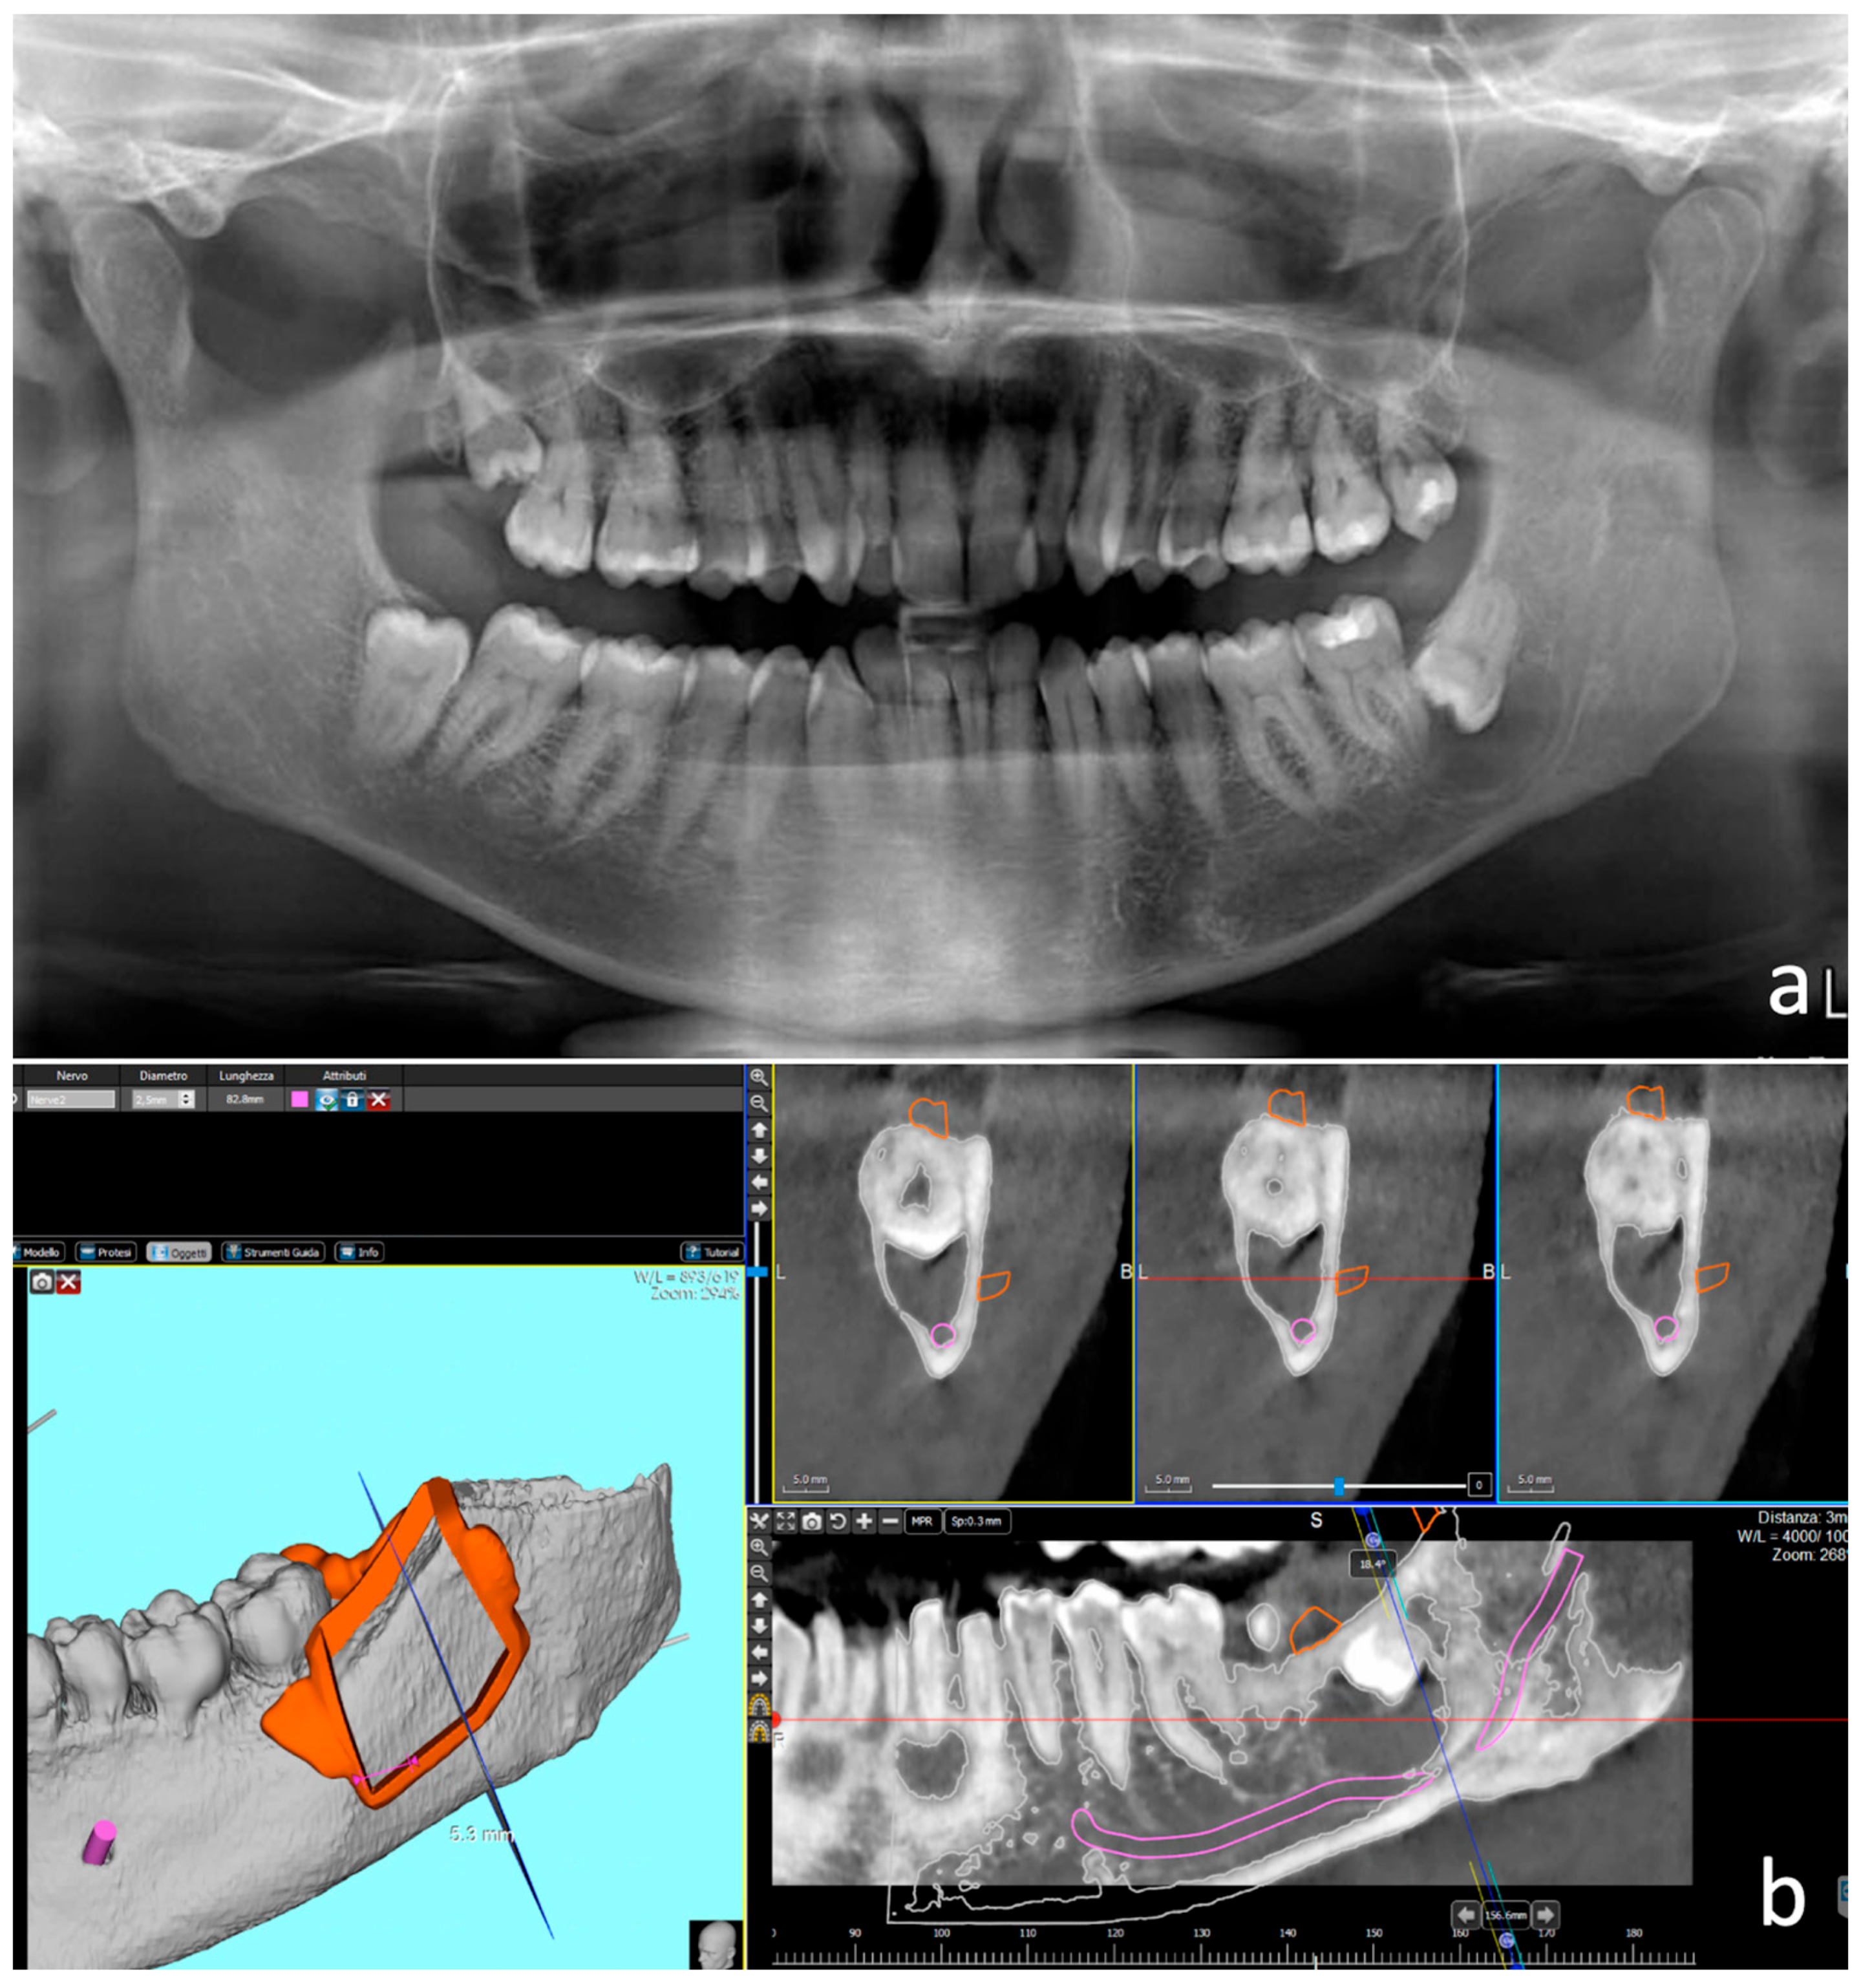

Two patients were referred for the extraction of clinically asymptomatic impacted left mandibular third molars. Informed consent was obtained and the two cases belonging to the case collection were approved by the Padova Hospital Ethical Review Board (Prot. 3719/AO/2016). The first patient, a 47-year-old healthy male, was referred for the suspicion of an odontogenic cyst associated with a horizontally oriented impacted tooth 38 incidentally discovered on a panoramic radiograph (case 1) (Figure 1). Case 2 consisted of a horizontally oriented deeply impacted tooth 38 in a 31-year-old healthy male patient, responsible for an increased probing depth distal to the adjacent second molar. In both cases, the unerupted teeth were close to the mandibular canal (Figure 2). Preoperative cone-beam computed tomography (CBCT) was performed in both cases, and the main inclusion criteria for the adoption of the technique were evaluated, namely, the considerable thickness of the buccal bone cortex at multiple points, i.e., >2 mm, and the need to enhance the control of the operatory field in the presence of anatomical limits (inferior alveolar nerve). CBCT allowed the design and production of a 3D printed surgical guide following the SafeCut® workflow (SafeCut®, GuidedSurgery2.0 s.r.l., Padova, Italy).

Figure 1.

Case 1. Odontogenic follicular cyst associated with fully included tooth 38. (a) Orthopantomography; (b) CT scan with the design of the cutting guide for the bone lid execution. The guide was designed with mixed bony and dental support, and stabilisation by a mesial fixation screw.

The Digital Imaging and Communication in Medicine (DICOM) datasets were processed with dedicated diagnostic and analytical software (3Diagnosys® 4.0, 3DIEMME®, Como, Italy). Structures such as the third molar, the pericoronal radiolucent area, the mandibular canal, and the roots of adjacent teeth were identified. Ideal bone-cutting planes were defined (angle and depth) in order to perform the osteotomies as close as possible to the roots of the adjacent teeth while avoiding any contact with them. The projections of the planned cutting planes allowed long-bevel osteotomies and the fashioning of a bone lid of adequate thickness and extent. The final guide design, including the anchorage to the adjacent teeth and the position of the stabilisation screw, was shaped using computer-aided design (CAD) software (PlastyCAD, 3DIEMME®, Como, Italy). The surgical guides were made of medical polyamide by means of a computer-aided manufacturing (CAM) process (3Dfast s.r.l., Padova, Italy) and were designed to have both dental and bone stabilisation. In case 1, the template had an internal cutting profile and an anterior fixation screw (Figure 1), whereas in case 2, the template appeared as a solid with an external guide profile. Furthermore, the fixation screw was envisaged in the centre of the solid, with the expectation of using the same bone hole to stabilise the bone lid at the end of the operation using a longer screw anchored to the lingual cortical bone.